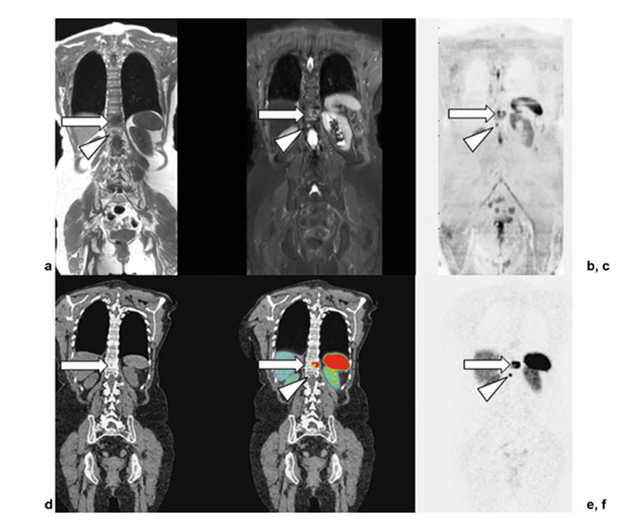

Hình 5. Hình ảnh cộng hưởng từ toàn thân đồng thời (WB-MRI) và chụp cắt lớp phát xạ positron/CT sử dụng octreotide (PET/CT) ở một phụ nữ 73 tuổi với u thần kinh nội tiết phổi. (a–c) Hình ảnh T1 toàn thân, STIR, DWI cho thấy một ổ lớn (mũi tên) và một ổ nhỏ (đầu mũi tên) có cường độ tín hiệu thấp (SI) trên T1, cường độ tín hiệu trung gian trên STIR, và cản trở khuếch tán tại hai đốt sống ngực liền kề (T11 và T12). (d–f) Tương quan PET/CT với 68Ga-DOTATATE. Hình ảnh CT, PET/CT hợp nhất và PET cho thấy các tổn thương hoàn toàn tương ứng trong thân đốt sống T11 và T12. Những tổn thương này là nguyên nhân gây xơ cứng xương mức độ nhẹ trên CT (hình d, mũi tên) và biểu hiện tăng bắt chất đánh dấu phóng xạ rõ rệt trên PET và PET/CT (hình e, f; mũi tên), qua đó chứng minh sự biểu hiện của thụ thể Somatostatin tại các ổ u.